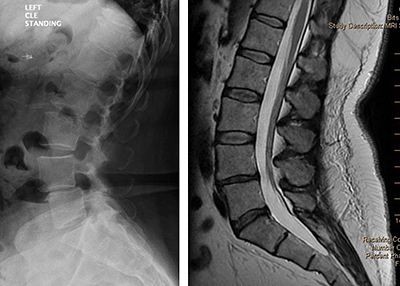

Review the routine radiograph in Figure 1A [left image]. The patient has a spondylolisthesis at L4-L5. Now review the MR image of the same patient in Figure 1B [right image]. Where did the spondylolisthesis go? The answer? Instability allowed the spondylolisthesis to reduce.

From reviewing the images in Figures 1A and 1B, common sense would suggest that when a spondylolisthesis is identified on a standing lateral view, an additional lateral view taken with the patient supine could be helpful. The goal is to detect the transition of the unstable segment, similar to the transition seen in Figures 1A and 1B.